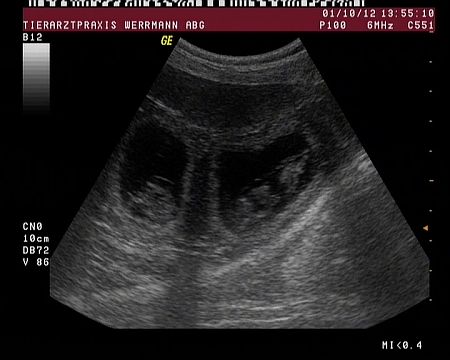

Auf diesem Bild ist sehr klar die Fruchtblase mit dem darin liegenden Welpen zu erkennen. Der Welpe ist 33 Tage alt.